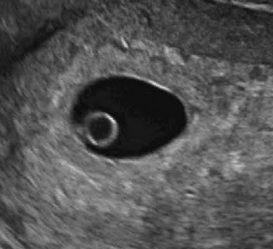

7 седмица